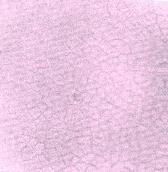

a) Upper epidermis

- (a) Surface view of the upper epidermis of the leaf showing the relatively small polygonal cells with their straight cell walls and cicatrices of detached covering trichomes.